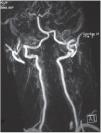

El resultado de la exploración cardiopulmonar y abdominal fue normal, las extremidades inferiores no presentaban edemas, los pulsos pedios estaban presentes y simétricos y en la exploración neurológica no se encontró rigidez de nuca ni alteración de pares craneales, no había signos de focalidad y la fuerza y sensibilidad eran normales. Se evaluó la marcha, que también era normal, con Romberg negativo. La tensión arterial fue 110/70 mmHg, frecuencia cardiaca de 75 pulsaciones por minuto y una temperatura de 36,2 oC. Tras esta primera valoración se derivó a la paciente a su domicilio con un tratamiento analgésico. Al cabo de 12 horas la paciente volvió por continuar con sus molestias. En esta ocasión, en la exploración neurológica se descubrió una hemihipoestesia izquierda, por lo que se deriva al hospital, donde se le practica una analítica general con resultados dentro de los parámetros normales y un estudio de resonancia magnética nuclear, en el que se observaron múltiples accidentes cerebrovasculares isquémicos (frontal izquierdo, talámico derecho, temporal posterior, occipital izquierdo y en ambos hemisferios cerebelosos). La angiografía y la angiorresonancia mostraron estenosis en segmento P1 de arterias cerebrales posteriores, de mayor importancia en el lado derecho, y un aneurisma en segmento V2 distal y mínima dilatación de la arteria vertebral en el segmento P2 contralateral, con muy leves irregularidades parietales en segmento V2 distal (figs. 1 y 2). Árbol carotídeo sin hallazgos. Es diagnosticada de DF.

Figura 1. Angiorresonancia magnética: estenosis en arterias cerebrales posteriores, de mayor importancia en el lado derecho, y aneurisma en arteria vertebral derecha.